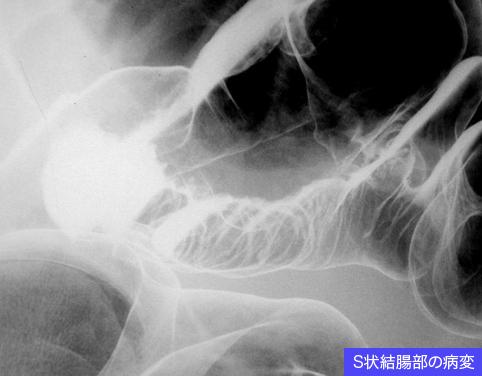

장간막지방조직염

장문막 지방조직염에 의한 다발성 장관협착의 수술예

대장/S상

X-P

40이상